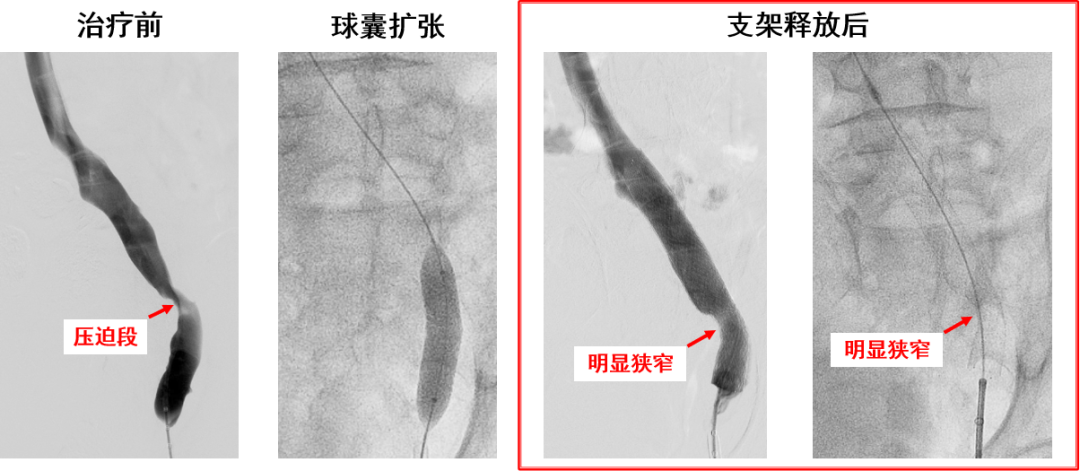

产品E:病例一(定位准确,柔顺性好)

产品E:病例二(多处受压)

产品E:病例三(径向支撑力不足?)

优点:

近心端斜口,防对侧血栓形成

有较强的径向支撑力

柔顺性良好

显影性能较好,定位精准

锥形支架设计,贴合血管解剖结构和形态

仅限用于髂总静脉,无延长段

近端径向支撑力略不足